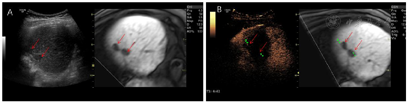

肝脏超声造影与增强MRI检查:S5、S8肿瘤呈"快进快退"表现,提示肿瘤复发。

根据患者的实际情况,MDT讨论一致同意行超声引导下微波消融治疗。超声-MR融合成像提示共4个病灶复发。S8有2个邻近膈面病灶,为保护膈肌及保证视野清晰,行人工胸水、人工腹水辅助,因腹腔粘连较严重,膈下腹水操作失败,仅行人工胸水减少肺气对视野的影响,从而进行超声引导下消融、超声造影-MR融合成像评估效果(图1);S5小病灶邻近门脉且灰阶超声显示不清,应用超声-MR融合成像定位引导消融,并使用超声造影复查效果(图2);S5大病灶邻近胃肠道,因腹腔粘连行人工腹水操作较困难,改为使用球囊隔离技术将肝肿瘤与肠道分离,在保证肠道安全的情况下行超声引导下消融,并行超声造影-MR融合成像评估效果(图3)。